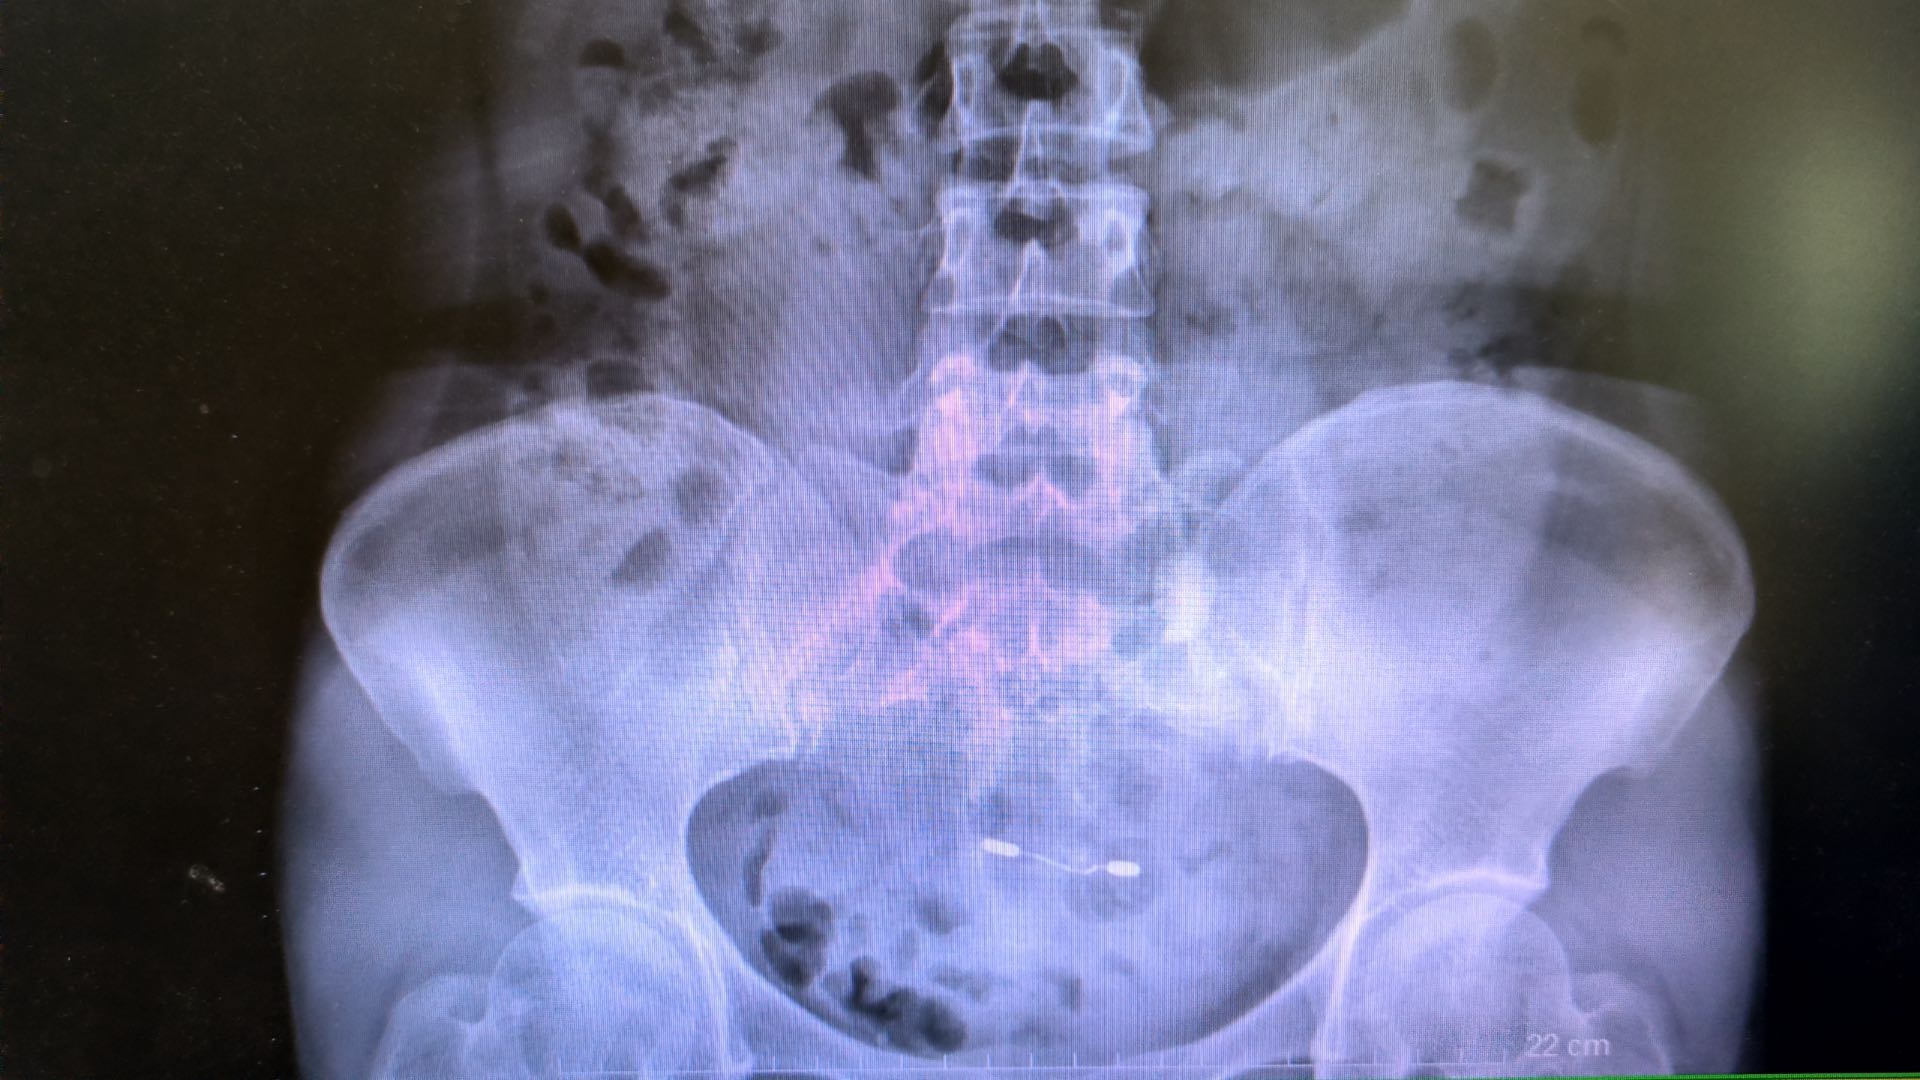

41岁的王女士平时经常腰部酸胀不适,腰痛反复发作,严重影响生活质量。11月25日上午,王女士左侧腰部剧烈疼痛,并持续两天,入住武汉市第五医院泌尿外科,经医生诊断为输尿管结石伴肾脏重度积水,石头直径超过2CM。考虑到王女士结石较大,且肾脏重度积水患者肾皮质较薄,使用传统输尿管镜碎石手术会造成肾内压力较大,容易产生肾破裂风险,武汉市第五医院泌尿外科主任李颢决定使用组合镜进行碎石并取石,相较于传统输尿管镜,组合镜优势在于碎石与取石可同步完成,微创近无创,并且大大降低重度肾积水患者碎石手术中因肾盂压力过高导致肾破裂的风险。

入院后第二天泌尿外科团队对王女士进行组合镜下输尿管碎石取石术,带有负压的组合镜在碎石过程中,通过持续的负压吸引将小结石同时吸出,大大减少了结石残留及移位进入肾脏的风险,同时也提高了取石效率。手术过程顺利,仅用20多分钟便顺利完成。术后第二天王女士便康复出院,随访结果腰部已无疼痛。

泌尿外科主任李颢介绍,组合镜是一种既可以碎石,又同步清石的治疗上尿路结石的新装备。组合输尿管硬镜经人体自然腔道逆行可视下进入人体的输尿管,运用钬激光把结石击碎呈粉末状,再通过负压鞘将其“吸”出体外,弥补了传统治疗方法“只碎石不排石”的弊端;还可根据手术操作过程中的需要,随时通过调节阀主动控制腔道内压力,防止术中腔道高压带来的系列风险,实现安全治疗。同时,如果肾内有结石或者输尿管较大残石进入肾盂、肾盏内,可以留置组合输尿管镜外鞘,一期置入输尿管软镜击碎肾内结石。